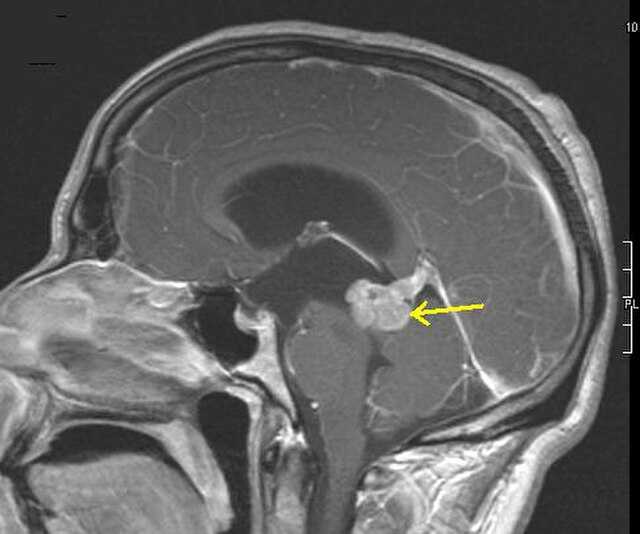

Bildgebung

Die Bildgebung erfolgt in der Regel mittels Magnetresonanztomographie. Eine Kontrastmittelaufnahme ist bei Grad-2-Astrozytomen selten (20 %), bei höhergradigen Subtypen jedoch häufig. Verkalkungen können vorliegen. Insbesondere höhergradige Tumoren können auch ein umliegendes Ödem zeigen.

Ein hochsensitives Merkmal für Astrozytome der Grade 2 und 3 ist ein T2/FLAIR-Mismatch, also ein Darstellungsunterschied zwischen zwei MRT-Sequenzen. In der T2-Sequenz zeigt sich der gesamte Tumorbereich hyperintens, also aufgehellt, während in der FLAIR-Sequenz nur der Randsaum hyperintens ist. In der T1-Sequenz ist der Tumor hypointens.

Astrozytome können auch als Zufallsbefund bei computertomographischen Untersuchungen finden. Grad 2 zeigt unscharfe Hypodensitäten, manchmal auch Verkalkungen oder zystische Formationen. Höhere Grade präsentieren auch Ödeme oder Kontrastmittelanreicherung. Insbesondere Astrozytome Grad 4 können sich ähnlich wie Glioblastome mit großen, zentralen Nekrosen mit umgebender Kontrastmittelanreicherung darstellen.